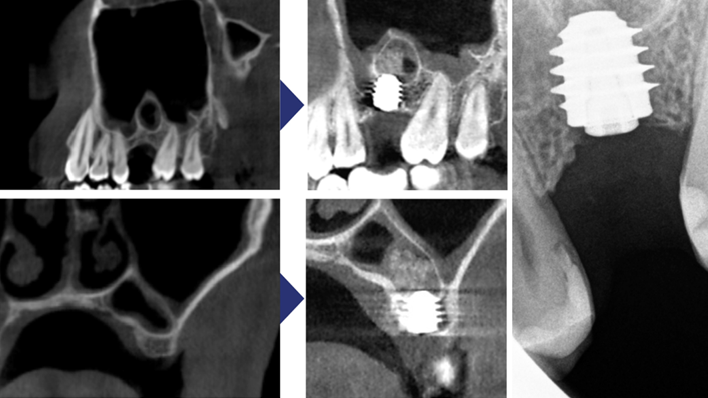

Clinical case: Delayed implant placement: sinus floor elevation by means of lateral

approach & implant placement with GBR

- Courtesy of Dr. Irfan Abas, Netherlands -

Clinical case: Installation of dental implants in complicated anatomic conditions using crest lifting methods

- Courtesy of Dr.Alexander Lysov, Russia -

Keywords

AnyRidge, complicated anatomic conditions, crest lift, MICA Kit, Dr. Alexander Lysov, bone regeneration, GBR, #26, maxillary posterior

Products:

AnyRidge implant system, MICA Kit